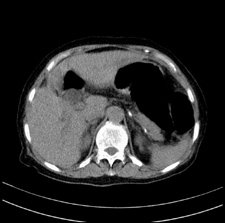

患者,女,75岁。腹痛,体黄5日,膝胸位时腹痛缓解。肝功能明日出来。彩超提示胆总管占位,未见血流信号。心电图提示s-t段改变。患者体质较弱,未能增强。

肝囊右.肾上腺囊肿

支持 胆总管结石,左侧胸膜增厚,心包膜增厚。